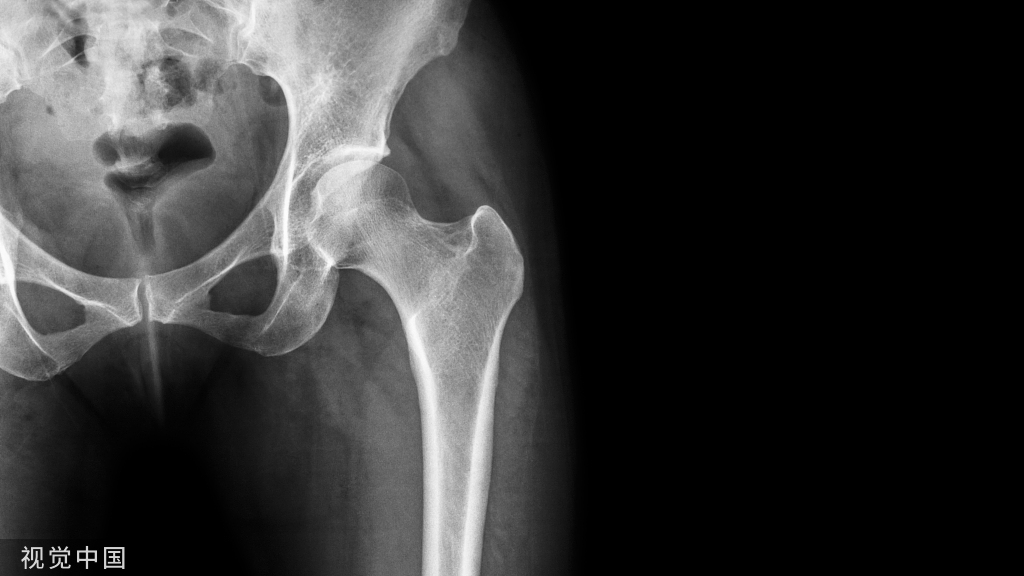

”骨水泥手术“ 病例展示

腰椎骨质疏松性骨折PVP

骨质疏松性骨折PVP